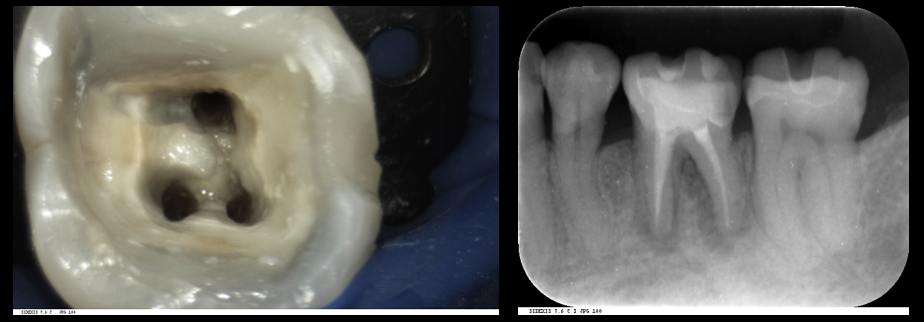

歯の根の治療(神経の治療)